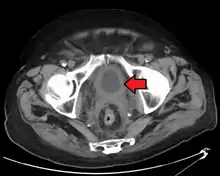

If invasive or high grade (includes carcinoma in situ) cancer is detected on TURBT, an MRI and/or CT scan of the abdomen and pelvis or urogram and CT chest should be conducted for disease staging and to look for cancer spread (metastasis).[56] Increase in alkaline phosphatase levels without evidence of liver disease should be evaluated for bone metastasis by a bone scan.[57] Although 18F-fluorodeoxyglucose (FDG)-positron emission tomography (PET)/CT has been explored as a viable method for staging, there is no consensus to support its role in routine clinical evaluations.[54]

The most common sites for bladder cancer metastases are the lymph nodes, bones, lung, liver, and peritoneum.[78] The most common sentinel lymph nodes draining bladder cancer are obturator and internal iliac lymph nodes. The location of lymphatic spread depends on the location of the tumors. Tumors on the superolateral bladder wall spread to external iliac lymph nodes. Tumors on the neck, anterior wall and fundus spread commonly to the internal iliac lymph nodes.[79] From the regional lymph nodes (i.e. obturator, internal and external lymph nodes) the cancer spreads to distant sites like the common iliac lymph nodes and paraaortic lymph nodes.[80] Skipped lymph node lesions are not seen in bladder cancer.[79]